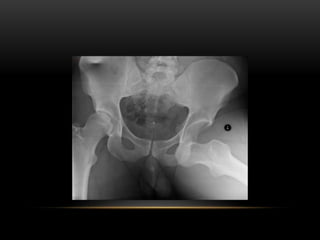

DISLOCATION OF

HIP JOINT

HIP JOINT DISLOCATION

According to direction of

femoral head displacement

• Posterior

• Anterior

• Central

POSTERIOR

DISLOCATION

• Dashboard injury

• Clinical features

• Short leg

• Adducted

• Internally rotated and slightly

flexed

• In every case of severe hip

injury X-RAY PELVIS.